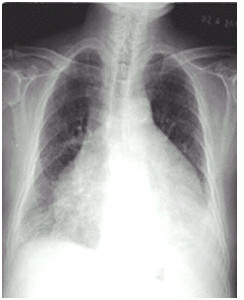

03卷-5.女性,63歲,咳嗽、咳痰、胸悶2月,伴下肢浮腫4天。診斷(本題滿分2.00分)

A.靴形心

B.正常心臟

C.普大型心臟

D.梨形心

本題答案:C

【該題針對(duì)“ X線-心臟增大(尖瓣型、主動(dòng)脈型和普大型) ”知識(shí)點(diǎn)進(jìn)行考核】